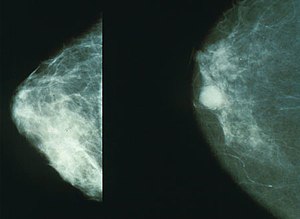

1. 유방암 초기증상

유방암 초기에는 증상이 명확하지 않을 수 있지만, 아래와 같은 변화를 주의 깊게 살펴보는 것이 중요합니다.

주요 초기증상

- 유방에 덩어리(종괴) 발생

유방이나 겨드랑이 부근에서 통증이 없는 단단한 혹이 만져질 수 있습니다. - 유방 모양 변화